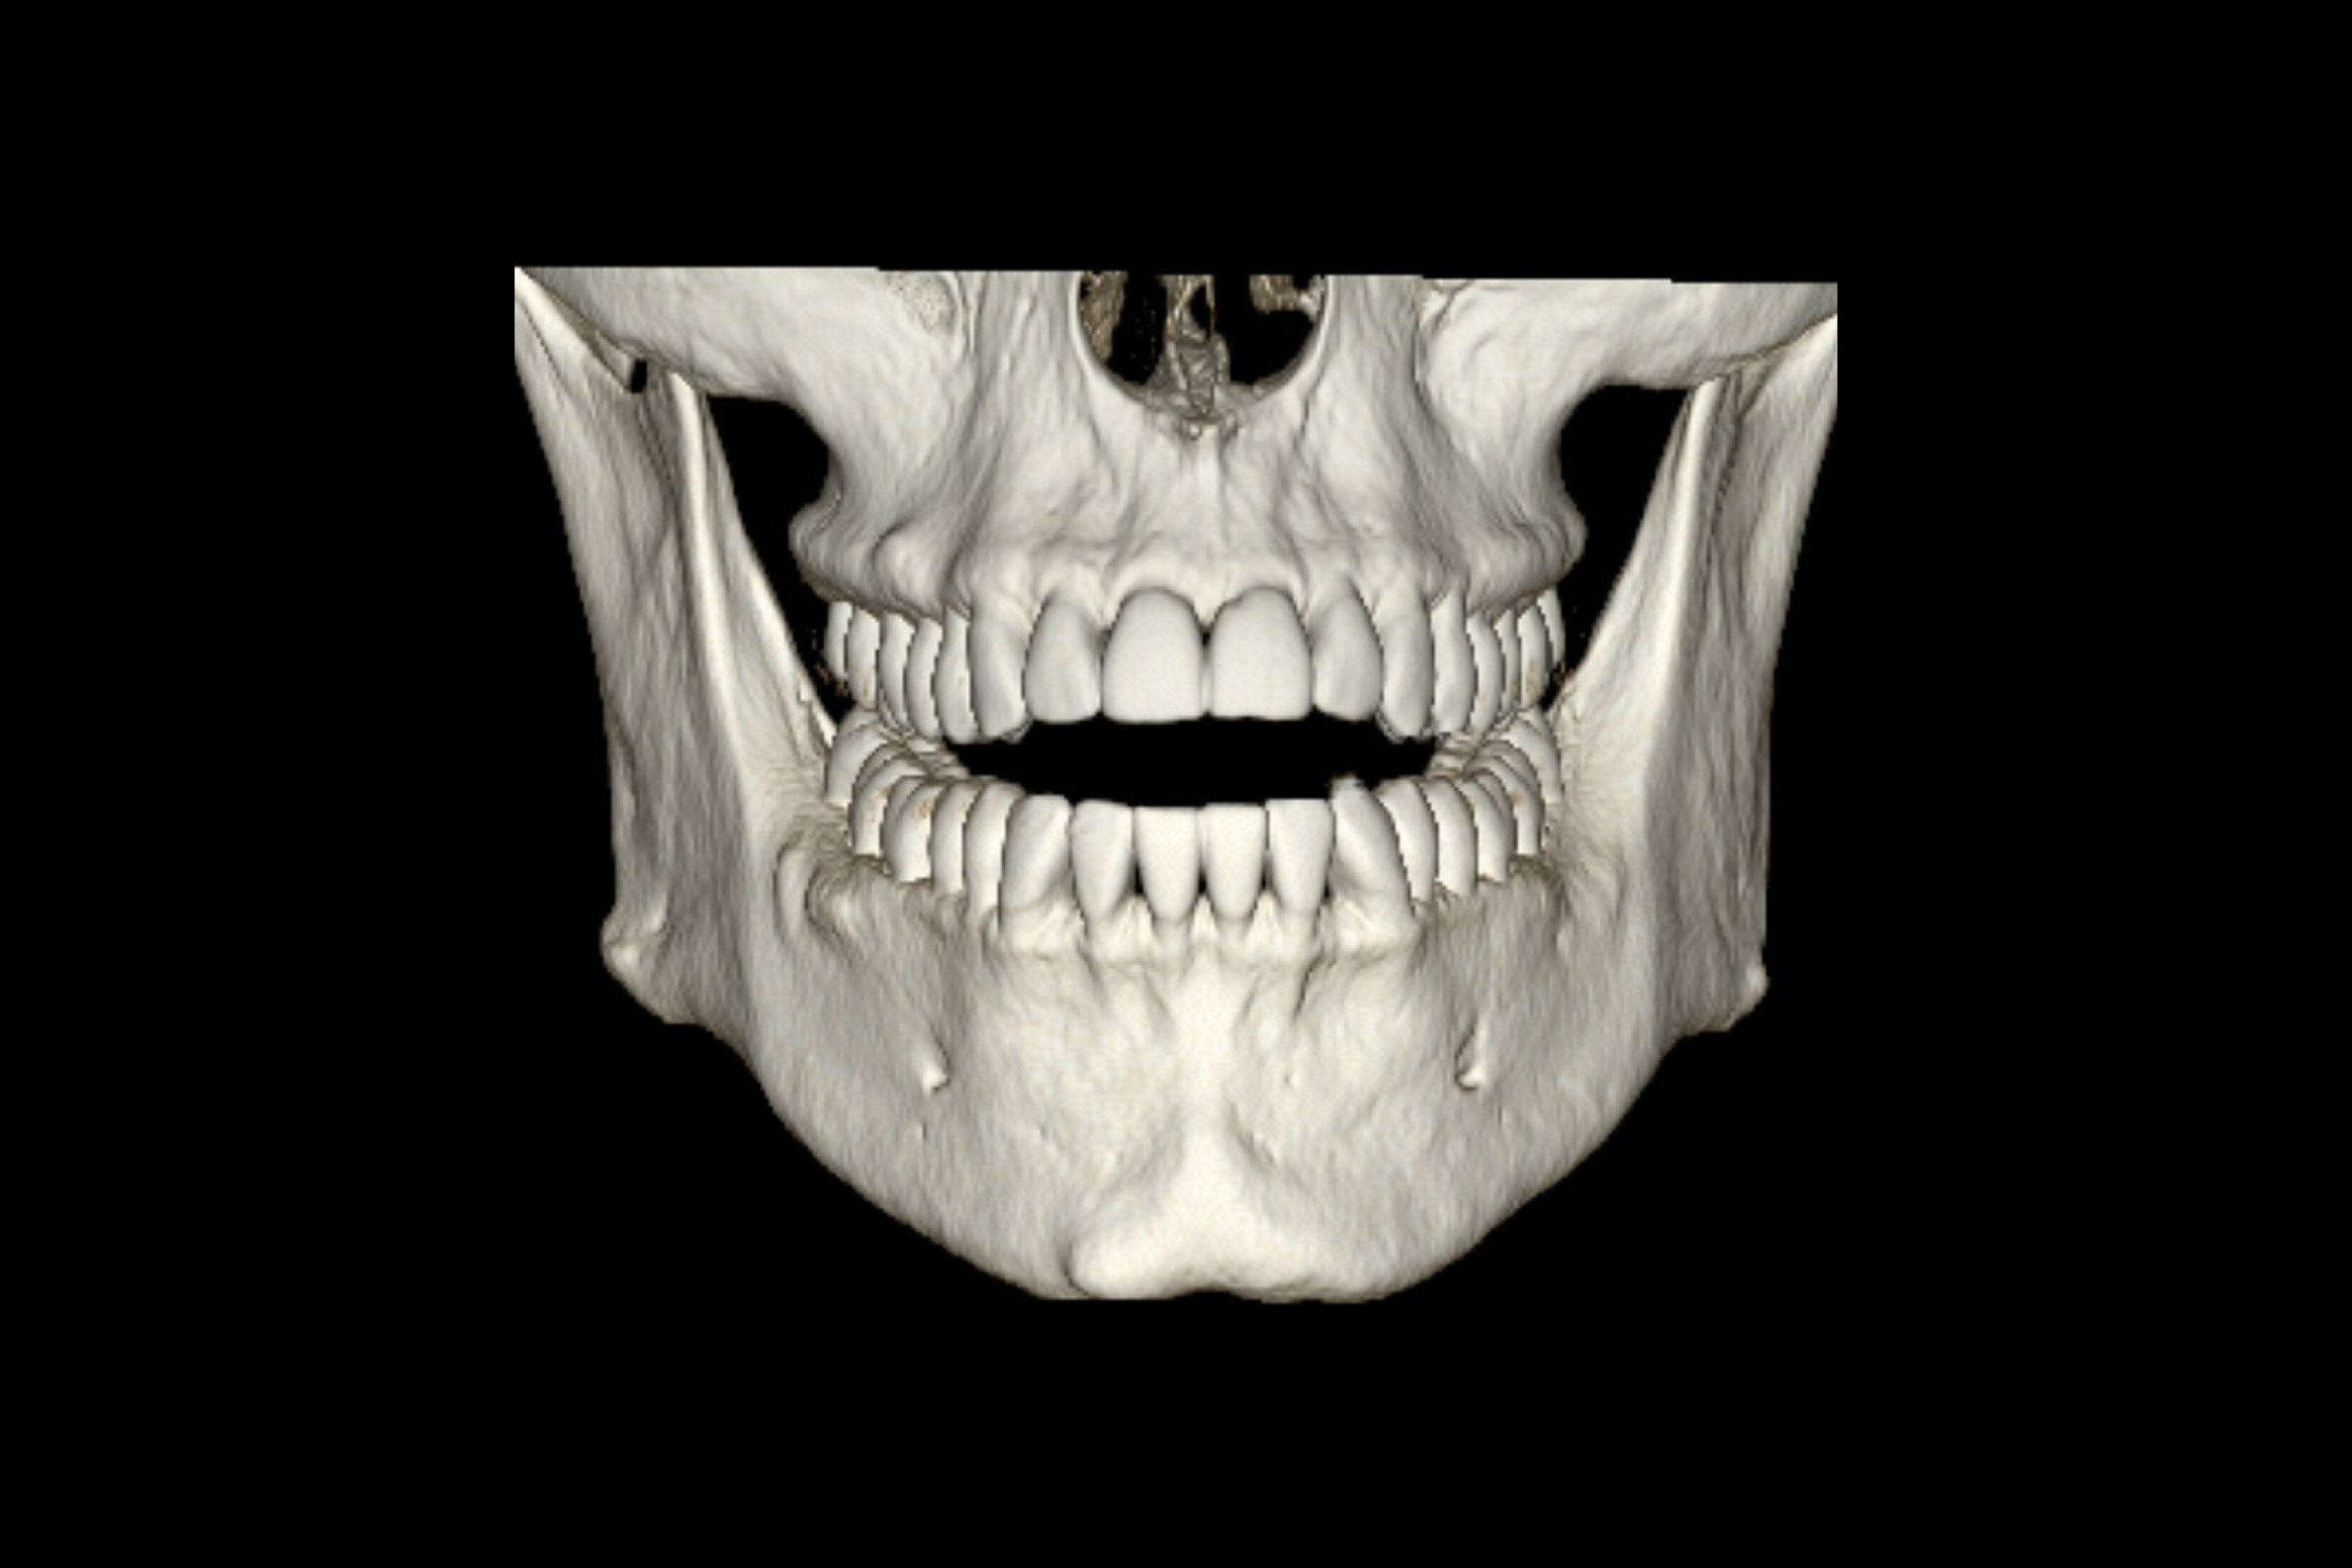

Avalie rapidamente rins e a bexiga com o Diagrama Renal

Simplifique a documentação e forneça acompanhamento fácil para pacientes com suspeita de hidronefrose. Não há necessidade de digitar os achados; simplesmente atribua um rótulo a partir de uma lista previamente preenchida que se correlaciona com imagens.

Revise imagens de segmentos de pulmão em uma única vista com o Diagrama Pulmonar

Um diagrama de visualização única de segmentos pulmonares anatômicos com armazenamento de imagem em um clique. Acompanha a avaliação pulmonar segmentar e pode ser útil ao mostrar tendências em resposta ao tratamento.